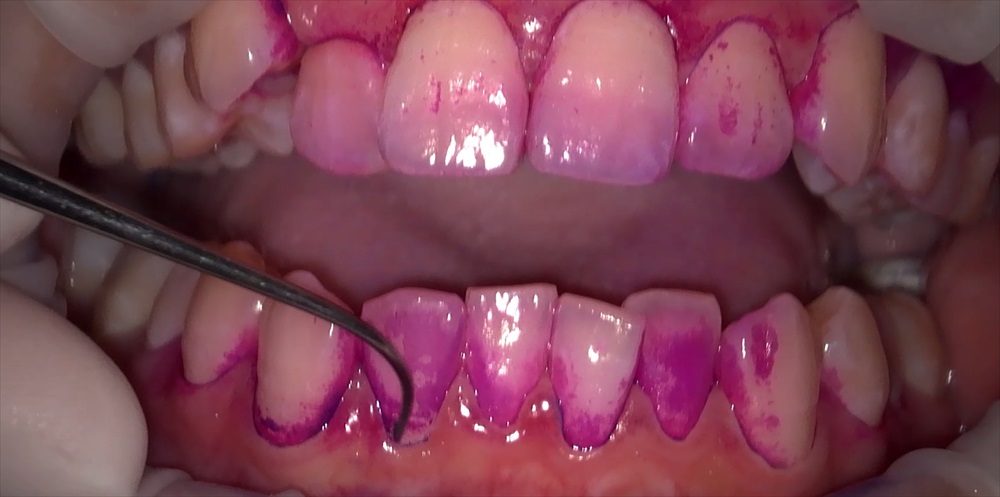

これです!!!

このピンク色に染まった所に細菌がいます!

これは歯垢(デンタルプラーク)と言います。

聞いたことあるかたもいると思いますがこの歯垢(デンタルプラーク)中に細菌が生息しています。

私達はバイオフィルムともいいます。

想像しにくいと思うので、歯垢1mg 中に約10億もの細菌が含まれているとい言われているらしく1mgの便に含まれる細菌の数は約1億と言われているので口腔内細菌の量が多いのです!!